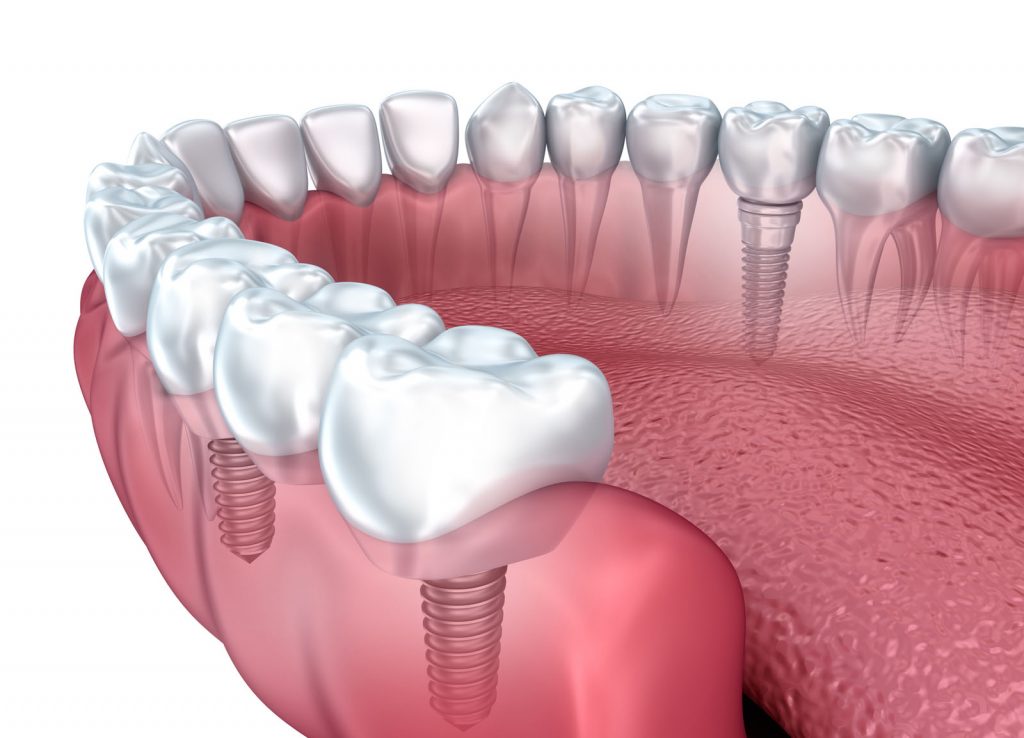

Bunlardan en uygununa karar verildikten sonra çene kemiğine implant yerleştirilir. İmplant tedavisi bir kişinin bir ya da daha fazla dişini kaybettiğinde ve yerine yeni diş yerleştirilmesini istediğinde gerçekleştirilen bir tedavi yöntemidir. Implant diş tedavisi iki aşamadan oluşmaktadır. İmplant tedavisinin süresi yapılacak olan implant sayısına ve hastanın çene kemiğine bağlı olarak yarım saat ile birkaç saat arasında da değişebilir.

İmplant tedavisinin süresi. Bazı markalar daha hızlı iyileşen modeller üretmiştir ve bu süre uygun vakalarda 20 güne kadar inebilmektedir. Konvansiyonel yaklaşımdacerrahisiden sonra alt çenede 8 hafta üst çenede ise 16 hafta kemik ile vidanın kaynaşması için beklenmelidir. Hekim dişe en uygun implantın hangisi olduğuna karar verir.